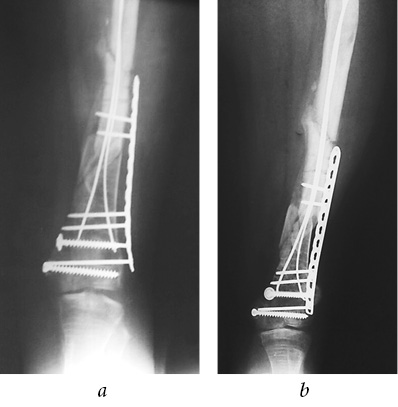

After the standard preoperative examination, surgical treatment was performed on the same day. To eliminate the blockade for the knee joint, the TEN was removed. Due to the pronounced displacement of fragments of the distal third of femur, comminuted nature of the fracture, and delayed consolidation, a mini-invasive osteosynthesis with a metaphysical plate 3.5 LCP was performed to ensure adequate reposition, stable fixation, and preservation of the periosteal blood circulation, (Fig. 8). Additionally, medial TEN shortening of the right femur was performed. After the surgery, the left lower extremity was immobilized with a rear polymer splint from the lower third of the shin to the upper third of the femur for a period of 10 days.

Fig. 8. Intraoperative radiographs of the left femur, mini-invasive osteosynthesis with a metaphysical plate (a); postoperative plain radiograph of the femurs in the frontal view (b)

One month after the surgery, the patient provided a radiograph of the left femur in one projection. Along with the osteosynthesis of the left femur with one TEN, the displacement of fragments was preserved in the distal third of the shaft and the delayed consolidation of the fracture and signs of TEN migration were noted (Fig. 6 a). The term of immobilization of the left lower limb was extended to a period of 8 weeks.

On the radiographs of the right femur, the current consolidation of the fracture was noted. Immobilization was discontinued and the patient proceeded to mobilize the right knee joint (Fig. 6 b, c).

Fig. 6. Radiographs of the left femur: signs of fragments displacement, delayed consolidation, TEN migration (a); frontal view of the right femur (b); lateral view of the right femur: signs of current consolidation (c)